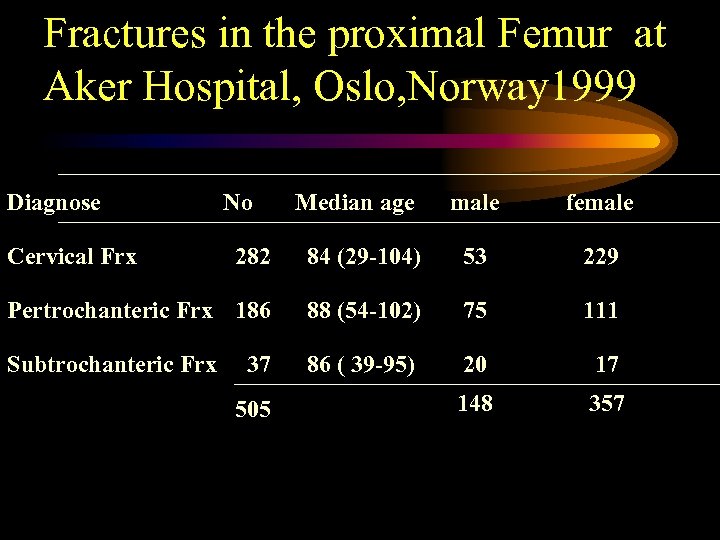

Fractures in the proximal Femur at Aker Hospital, Oslo, Norway 1999 Diagnose Cervical Frx No Median age male female 282 84 (29 -104) 53 229 Pertrochanteric Frx 186 88 (54 -102) 75 111 Subtrochanteric Frx 86 ( 39 -95) 20 17 148 357 37 505

Fractures in the proximal Femur at Aker Hospital, Oslo, Norway 1999 Diagnose Cervical Frx No Median age male female 282 84 (29 -104) 53 229 Pertrochanteric Frx 186 88 (54 -102) 75 111 Subtrochanteric Frx 86 ( 39 -95) 20 17 148 357 37 505